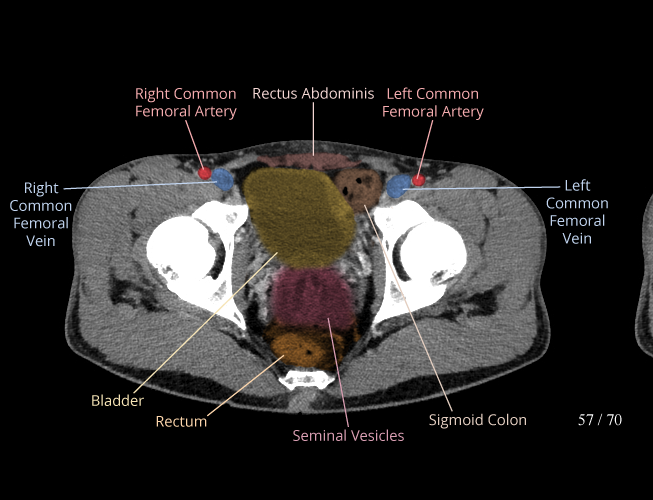

Body

Covers abdominal CT anatomy.

Pelvis

Covers pelvic MRI anatomy.